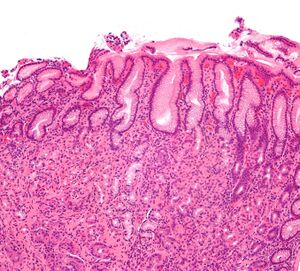

Gastritis helicobacter - intermed mag.jpg

صورة مجهرية لالتهاب المعدة . صبغة الهيماتوكسيلين والإيوسين.